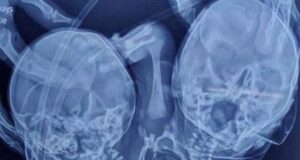

Bebé sorprende al nacer con dos cabezas, tres manos y dos corazones

El nacimiento de un bebé le ha dado la vuelta al mundo después de nacer con dos cabezas, tres manos y dos corazones a causa de una extraña condición médica. Una mujer de la India, Shaheen Khan, que en un principio esperaba creía estar embarazada de un par de gemelos de acuerdo …